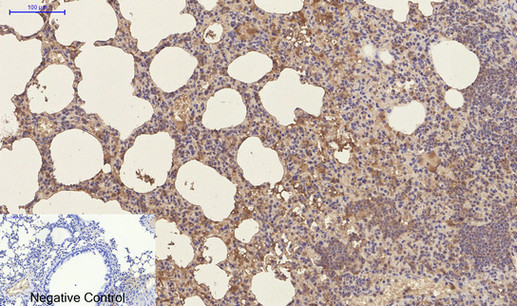

Immunohistochemistry analysis of paraffin-embedded mouse lung tissue using CD23 antibody.High-pressure and temperature Sodium Citrate pH 6.0 was used for antigen retrieval. Negative control was used by secondary antibody only.